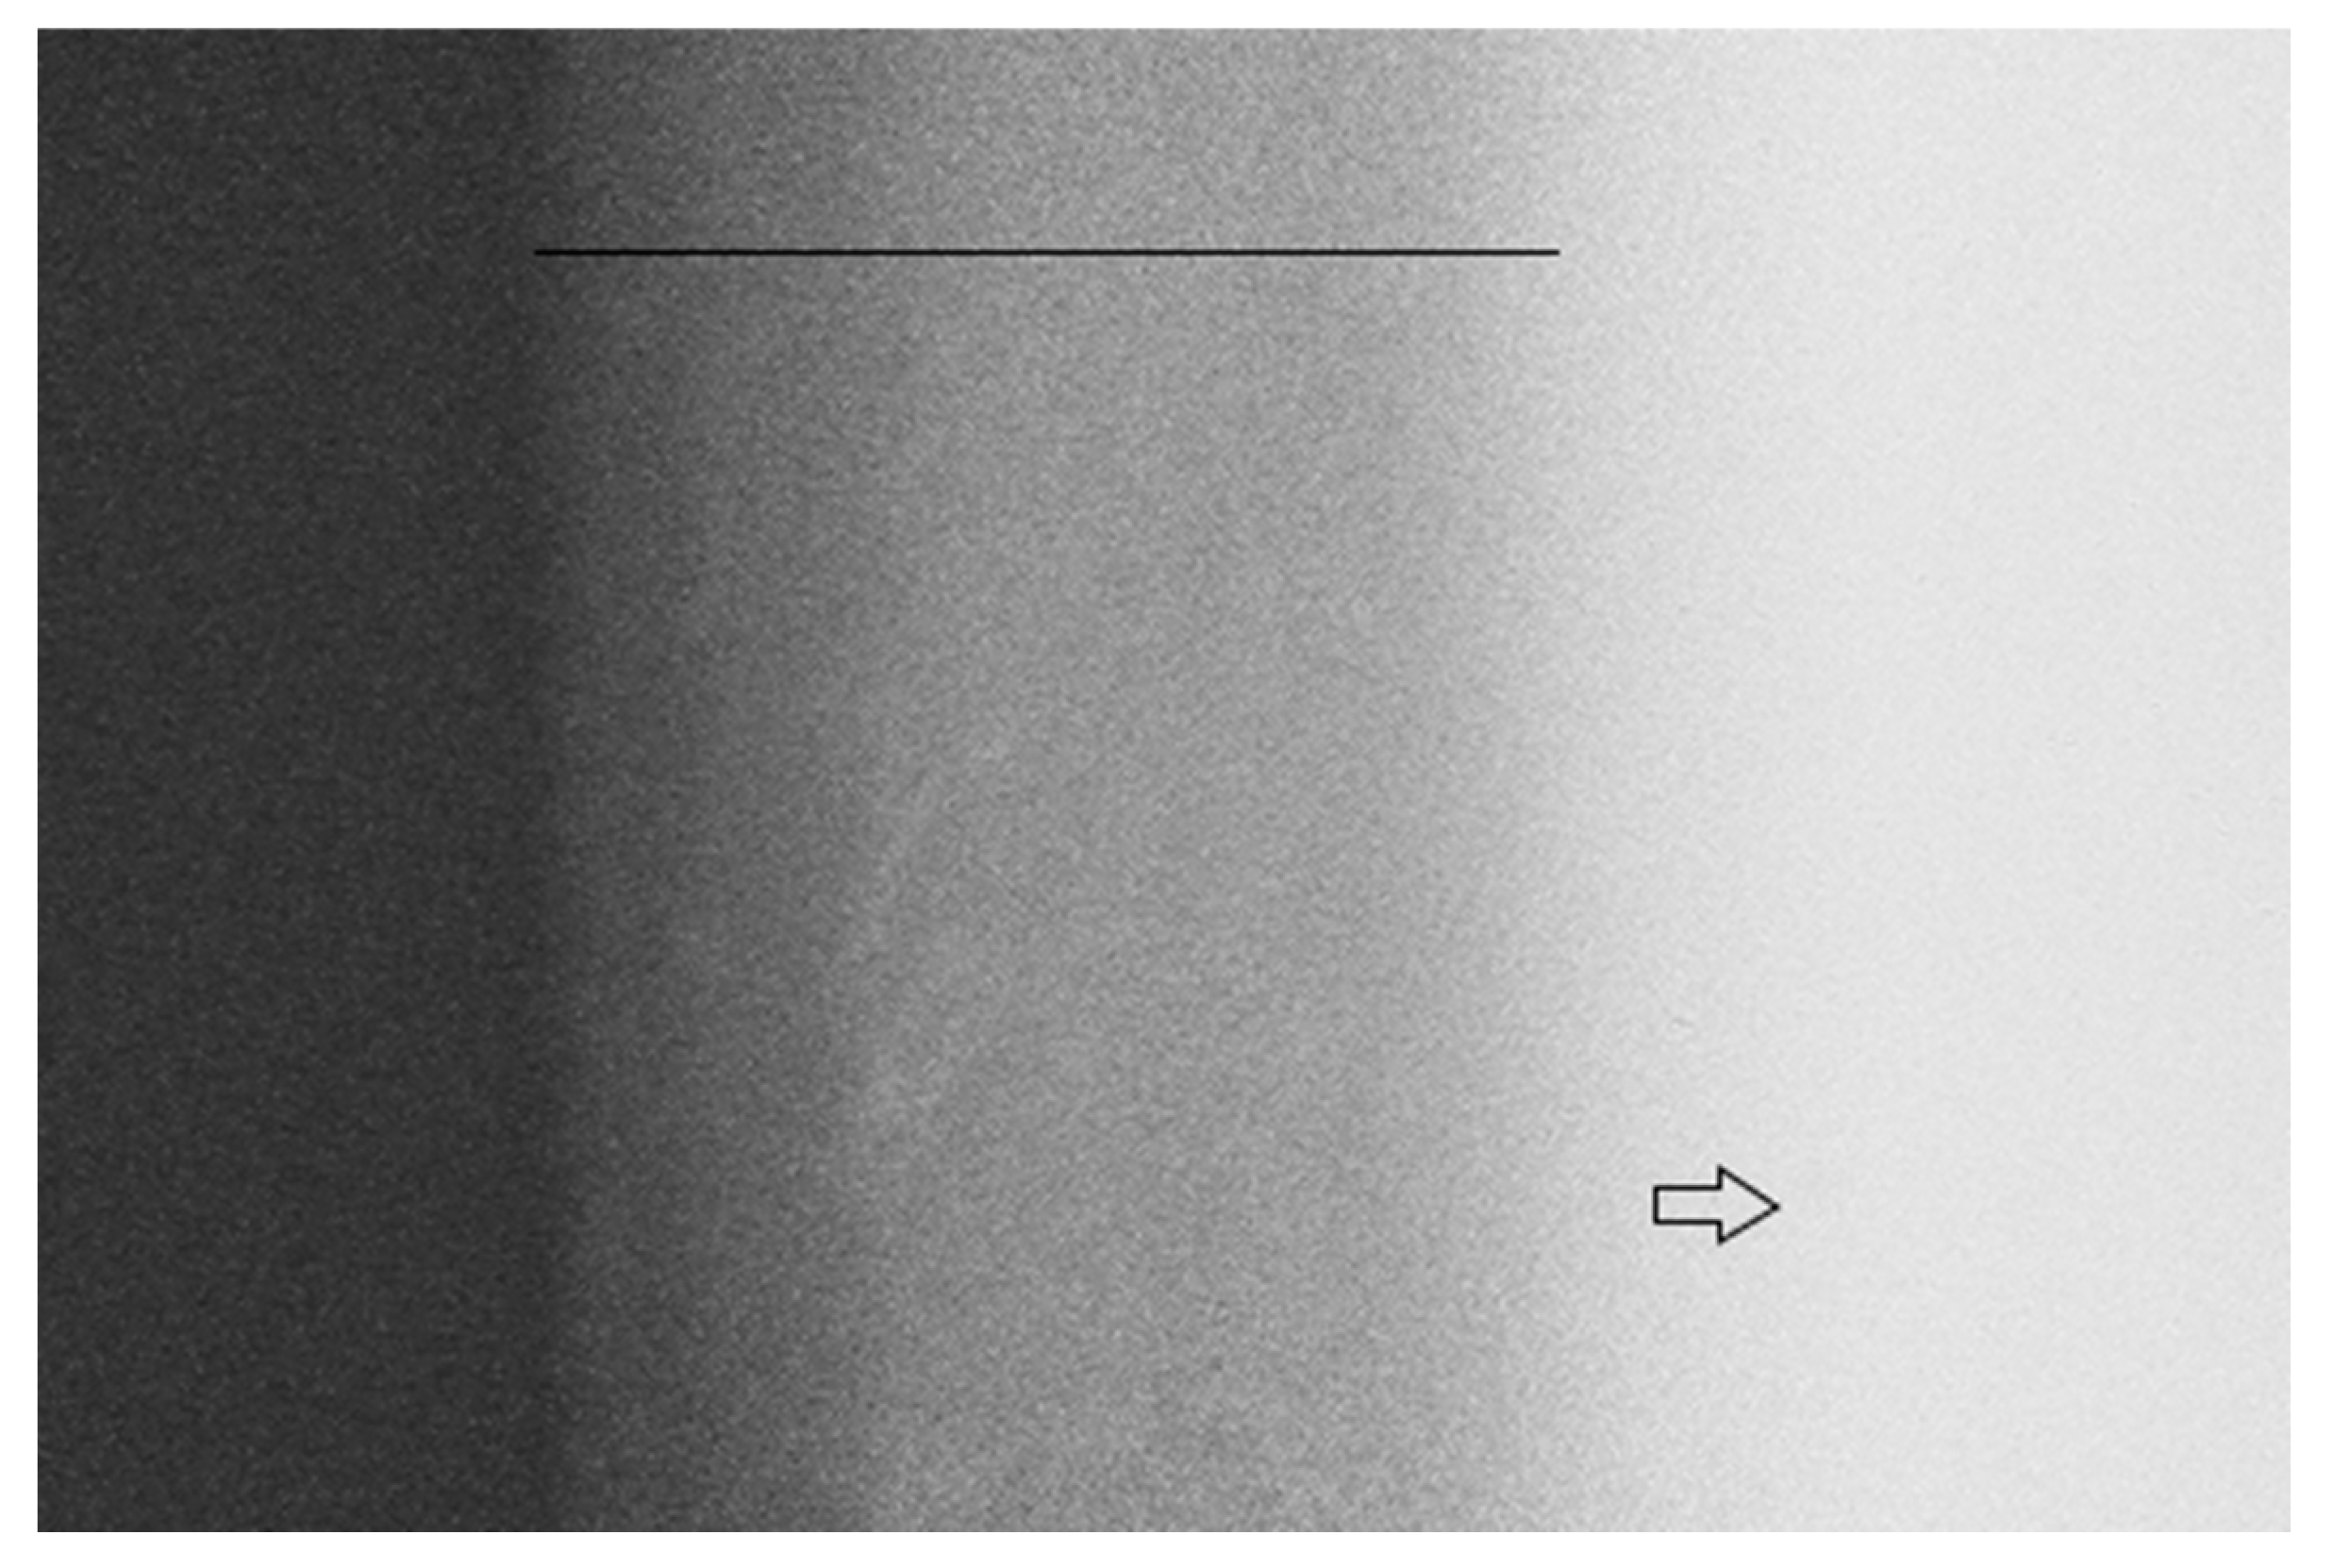

Figure 1 shows a representative image of the dentin specimen after the caries-like dentin induction (7 days in a caries solution). The radiolucent area confirms that the protocol used was sufficient to induce a caries-like dentin lesion with an adequate depth and mineral loss (Table 2).

Figure 1.

Representative TMR image of the dentin after caries-like dentin induction via the biological model. The line indicates a radiolucent zone suggesting caries-affected dentin due to the demineralization process. The arrow indicates a radiopaque zone suggesting sound dentin that was not demineralized.

During the in vitro induction of a caries-like dentin, the position of the specimen is crucial to allow for active bacterial colonization over the dentin’s surface [54], simulating the formation of a real biofilm. Thus, the specimens were vertically suspended into the well, avoiding the gravity action and the formation of a sedimented cell layer [54]. In addition, two species of caries-related bacteria (S. mutans and L. acidophilus) were used to fulfill the current paradigm that the bacteria from the oral cavity are part of a complex, dynamic and interactive microbial community instead of using only one species as the etiologic agent of caries lesions [55,56]. Considering the above-mentioned information and based on the TMR results, we can state that the model and the time of induction used were enough to develop caries-like dentin lesions with an adequate depth (213.9 μm) and morphology for further experiments (Figure 1; Table 2).